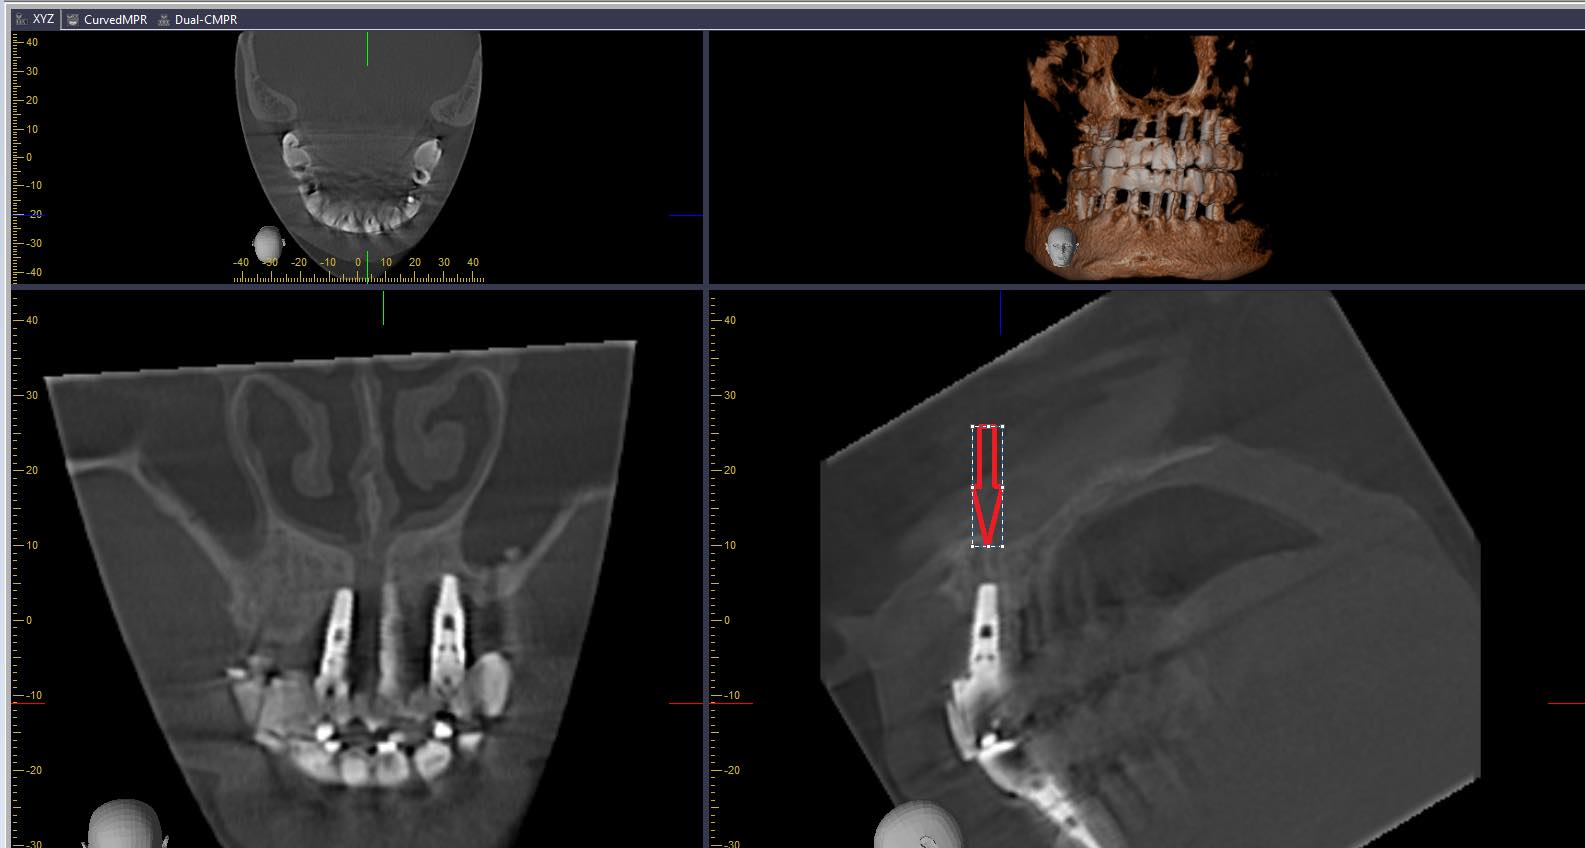

HÌNH 1-33 Xác định các cấu trúc được chỉ định.

Phân tích các yếu tố giải phẫu trên phim X-quang PA này, kết hợp với hình minh họa (A) để có cái nhìn chi tiết về vùng răng nanh và tiền hàm hàm trên. Trên Hình ảnh minh họa (A): Hình ảnh này mô tả các cấu trúc giải phẫu của răng nanh và tiền hàm hàm trên, cùng với mối quan hệ gần gũi với xoang hàm và hốc mũi. 1. Phục hình trám răng (Restoration / Filling): Vật liệu trám răng cản quang trên thân răng. 2. Đường nối men – xi măng (Cemento-enamel junction – CEJ): Nơi men răng và xi măng chân răng gặp nhau. Mũi tên chỉ rõ vị trí này. 3. Xoang hàm (Maxillary sinus): Khoang chứa khí lớn trong xương hàm trên, xuất hiện dưới dạng vùng thấu quang (tối) nằm phía trên các chóp răng tiền hàm và răng hàm. 4. Sàn xoang hàm (Floor of maxillary sinus): Một đường cản quang hình cung hoặc hình chữ Y, tạo thành bờ dưới của xoang hàm. Đây là một cấu trúc giải phẫu rất quan trọng và thường thấy trên phim X-quang vùng răng hàm trên. Mũi tên chỉ rõ sàn xoang hàm. Trên Phim X-quang thực tế (B): Đây là một phim X-quang quanh chóp (PA) của vùng răng nanh và răng tiền hàm hàm trên.

• Các cấu trúc giải phẫu xoang hàm:

• Sàn xoang hàm (Floor of maxillary sinus): Rất rõ ràng là một đường cản quang (trắng sáng) hình cung chạy ngang qua phía trên chóp các răng tiền hàm và răng nanh. Sàn xoang hàm có vẻ lượn sóng và nằm rất gần các chóp răng.

• Xoang hàm (Maxillary sinus): Vùng thấu quang (tối) lớn nằm phía trên sàn xoang hàm. Phim này cho thấy một phần đáng kể của xoang hàm.

Đánh giá tổng thể trên phim X-quang (B): Phim này cho thấy các răng nanh và tiền hàm hàm trên với các phục hình trám răng. Các cấu trúc giải phẫu của răng và xương có vẻ bình thường. Cấu trúc quan trọng nhất được nhận diện rõ ràng là sàn xoang hàm và xoang hàm. Sàn xoang hàm nằm rất gần với chóp các răng tiền hàm, đây là một yếu tố quan trọng cần xem xét trong các thủ thuật nha khoa ở vùng này để tránh các biến chứng liên quan đến xoang. Không có dấu hiệu rõ ràng của sâu răng tiến triển hoặc viêm quanh chóp lớn trên phim này.